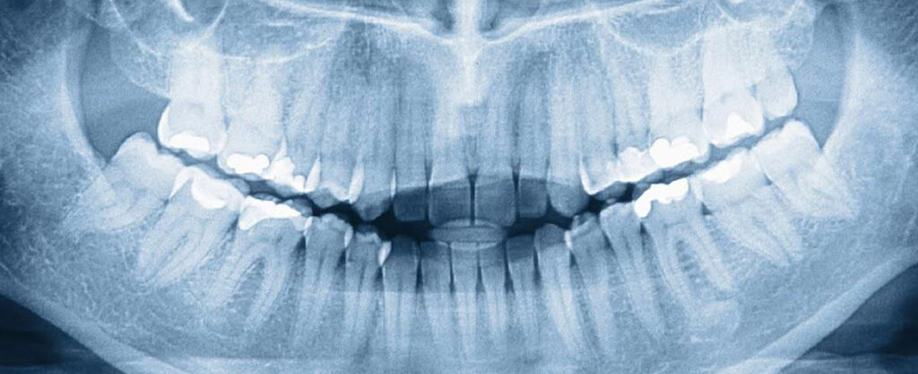

Oral Diagnoz ve Radyoloji Hakkında Merak Edilenler

Diş hekimi muayene sorasında diş çürüklerini, dişeti hastalıklarını ve kapanış sorunlarını tespit eder. Yapılacak radyolojik görüntüleme ise arayüz çürükleri, k

Diş hekimi muayene sorasında diş çürüklerini, dişeti hastalıklarını ve kapanış sorunlarını tespit eder. Yapılacak radyolojik görüntüleme ise arayüz çürükleri, kök ucu enfeksiyonları ve gömülü dişler gibi gözle görülmeyen pek çok sorunu gözler önüne serer.

Oral diagnoz zorunlu mudur?

Oral diagnoz sorunların en doğru şekilde tespit edilebilmesi ve hasta için en uygun tedavi planının çıkartılabilmesi için gereklidir.